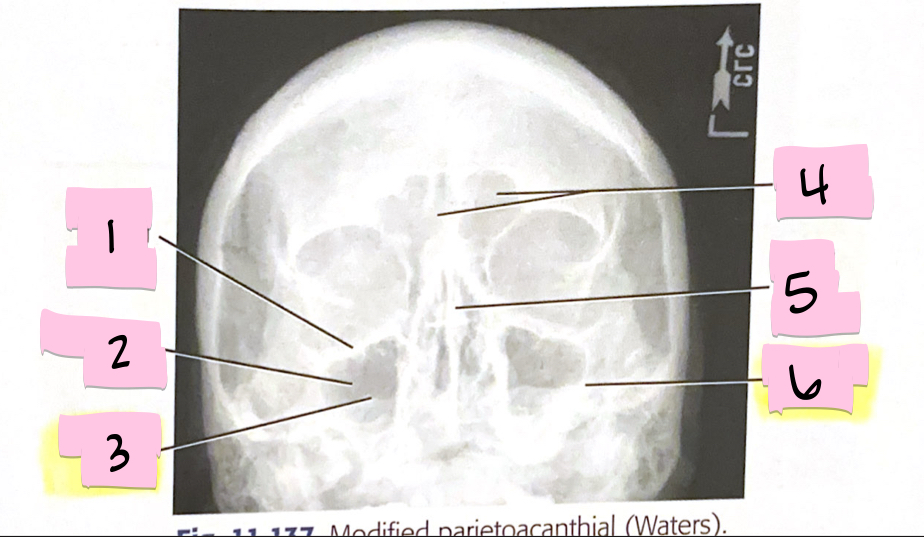

What is 1 pointing to?

Inferior orbital margin

What is 2 pointing to?

Maxillary sinus

What is 3 pointing to?

Petrous ridge

What is 4 pointing to?

Frontal sinuses

What is 5 pointing to?

Bony nasal septum

What is 6 pointing to?

Petrous ridge